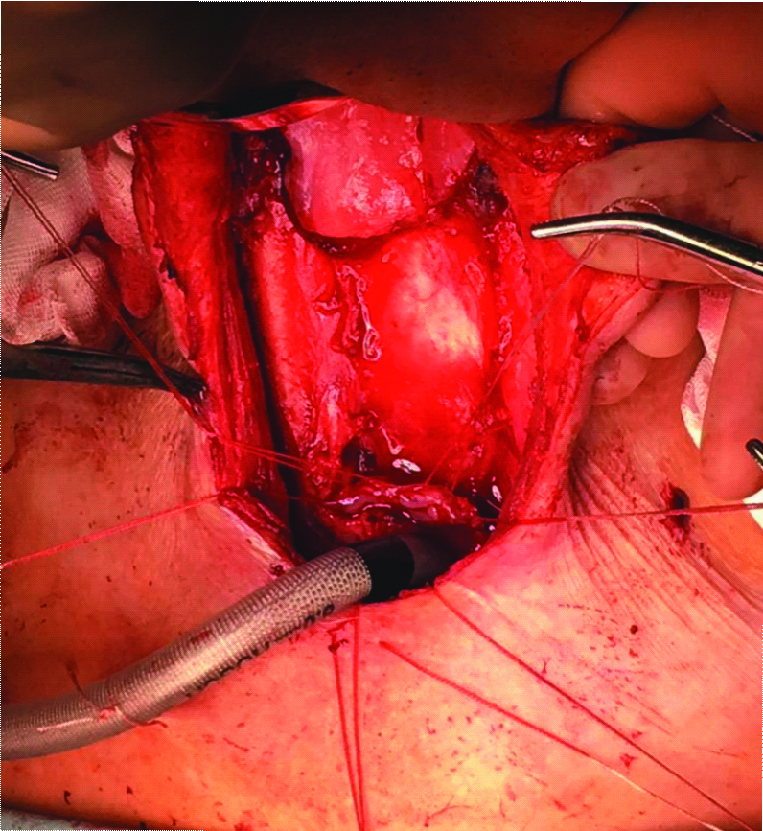

The surgical stages are presented in Figures 2–6.

Figure 2. Type of specimen removed: laryngopharynx, cervical esophagus

Рисунок 2. Вид удаленного препарата: гортаноглотка, шейный отдел пищевода.

Figure 3. View of the wound on the neck after extirpation: pharynx and cervical esophagus are removed, at the bottom of the wound is the prevertebral fascia. In the upper section of the wound, the borders of the pharynx are visualized, in the lower section of the wound – the remaining part of the esophagus

Рисунок 3. Вид раны на шее после экстирпации: глотка и шейный отдел пищевода удалены, на дне раны – предпозвоночная фасция. В верхнем отделе раны визуализируются границы глотки, в нижнем отделе раны – оставшаяся часть пищевода.